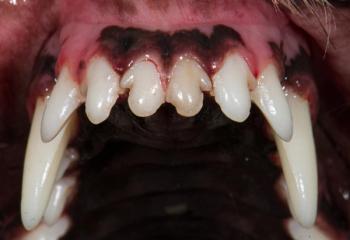

Most of the tooth is located below the gumline and out of view. Intraoral radiography can yield invaluable diagnostic information about your patients’ oral health.